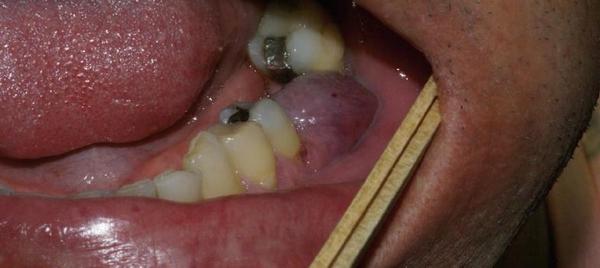

Гранулёма: что это такое

Напоминает небольшой мешочек (около 0,5 см), окружённый грануляционной тканью, как капсулой. Внутри — воспалительная жидкость. Место расположения — верхушка зуба. Это эпицентр заболевания. Задача такого осложнения: разрушить здоровую ткань зуба. Воспалительный очаг нельзя оставлять без лечения, так как дальнейшее бездействие приведёт к нарушению многих систем организма.

Фото 4. Гранулёма, возникшая из-за периодонтита. Представляет из себя припухлость на десне.